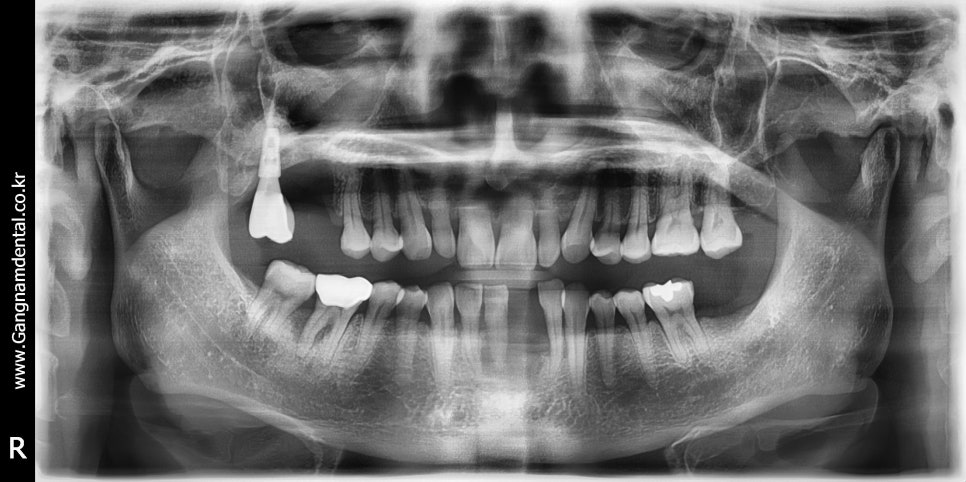

오늘은 37번에 임플란트를 심게 되었다. 사실 사랑니 발치 하려고 원장님 사랑니발치 교과서 1회독 한번 더 하고 올라왔는데, 내가 발치 예약 잡은 분이 코로롱 때문인지 오늘 못오신다고 그래서 발치는 못했다. 다음번엔 꼭 사랑니 발치 해야지..! 아무튼 그래도 저번에 36,37 임플란트 심어봤기 때문에 이번엔 나름 자신...

출처 아카이브 열기오늘은 37번에 임플란트를 심게 되었다. 사실 사랑니 발치 하려고 원장님 사랑니발치 교과서 1회독 한번 더 하고 올라왔는데, 내가 발치 예약 잡은 분이 코로롱 때문인지 오늘 못오신다고 그래서 발치는 못했다. 다음번엔 꼭 사랑니 발치 해야지..!

아무튼 그래도 저번에 36,37 임플란트 심어봤기 때문에 이번엔 나름 자신감과 이런저런 계획을 갖고 시작은 했지만, 성별의 차이때문이었는지 그냥 골질이 달라서 그런건지 그때랑은 또 달랐다.

전에 여성환자분께는 4.5파이 드릴링하고 4.5파이 수월하게 심었는데 이번엔 5.0드릴링 하고 5.0심는데도 빡빡하게 들어갔다. 5.5드릴을 절반정도만 담궈서 코로날부위만이라도 좀 쉐이핑을 하고 했으면 훨씬 나았을텐데 막상 지금 단계에 정신이 팔리니 배운것도 잘 못써먹더라. 픽스쳐가 빡빡하게 들어가니 환자분께서도 좀 불편해하셨다.

방향은 만족스러웠고 다만 픽스쳐 길이와 깊이에 아쉬움이 좀 남는다. 36distal bone에 스타퍼가 걸리는 문제 때문에 총 1시간이 넘게 걸렸고 환자분께서 아파하셔서 드릴링을 또 한번 하기가 내 마음이 아파서 픽스쳐 길이 안바꾸고 5mm 힐링 달고 마무리 했다. 사실 중간에 4.5 심었는데 7mm힐링 달았더니 김영삼원장님께서 보시곤 7mm빼고 5mm로 하라고 하셔서, 7mm힐링 풀다가 (조일 때 너무 꽉 쪼여놔서)픽스쳐도 같이 빠지긴 했는데~ 그 덕에 4.5에서 5.0으로 쉽게 바꿨다ㅋㅋ;; 한단계 덜어줬다..ㅋㅋㅋ...ㅋㅋ🤣